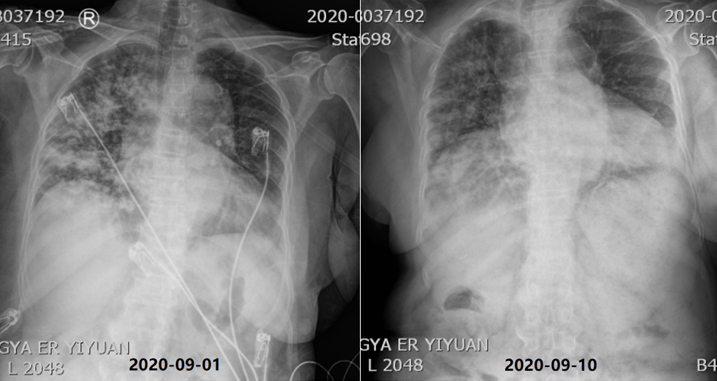

哌拉西林他唑巴坦4.5 g ivgtt q8h覆盖厌氧菌;细辛脑化痰;甲泼尼龙40 mg ivgtt qd(9月3-13日)、32 mg po qd(9月14日起)抗炎;泮托拉唑钠肠溶胶囊护胃,胰岛素降糖等治疗;9月4日转入普通病房,9月15日出院。治疗后患者右肺病灶较前明显吸收(图5)。出院前胸部X线片可见肺部病变较前明显好转(图6)。①外源性脂质性肺炎,Ⅰ型呼吸衰竭;②医院获得性肺炎;③糖尿病(分型未确定);④不完全性肠梗阻;⑤甲状腺肿大并结节;⑥低蛋白血症;⑦电解质紊乱;⑧右肾囊肿。出院后患者在当地医院住院20余天,激素每周减1片,复查胸部CT较前好转,但未完全吸收,后未再复查胸部CT。